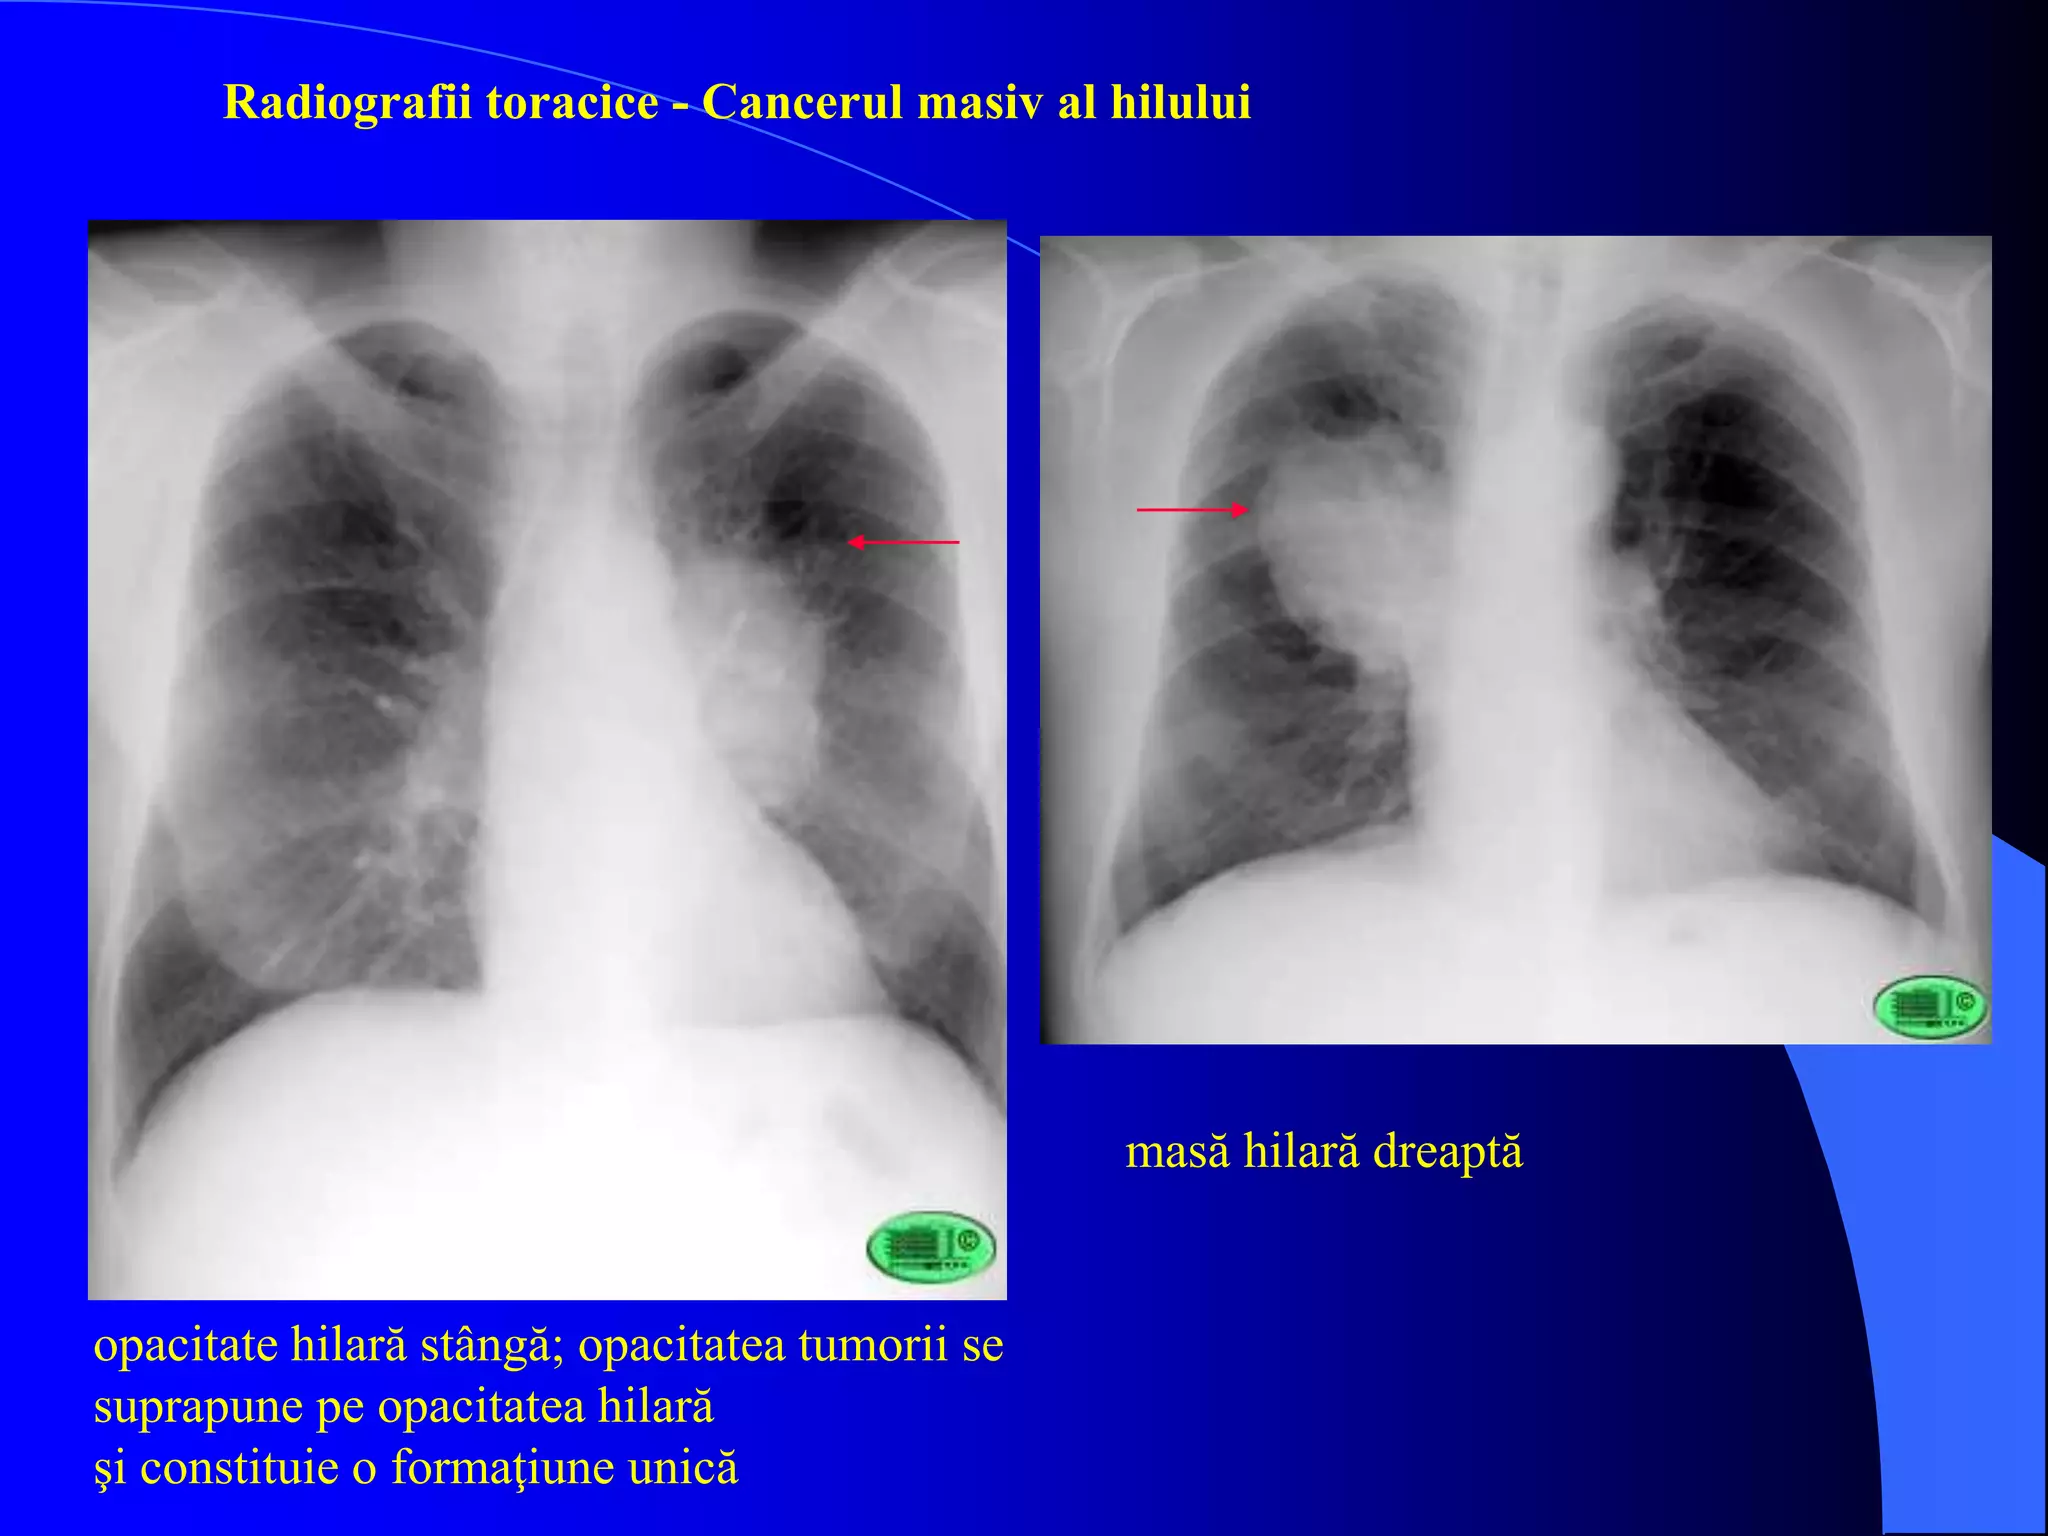

 radiografia si radioscopia toracica

- contur anormal al umbrelor hilare mediastinale

- condensari atelectatice, reactii pleurale

- una/mai multe formatiuni tumorale intraparenchimatoase

opacitate hilară stângă; opacitatea tumorii se

suprapune pe opacitatea hilară

şi constituie o formaţiune unică

masă hilară dreaptă

Radiografii toracice - Cancerul masiv al hilului